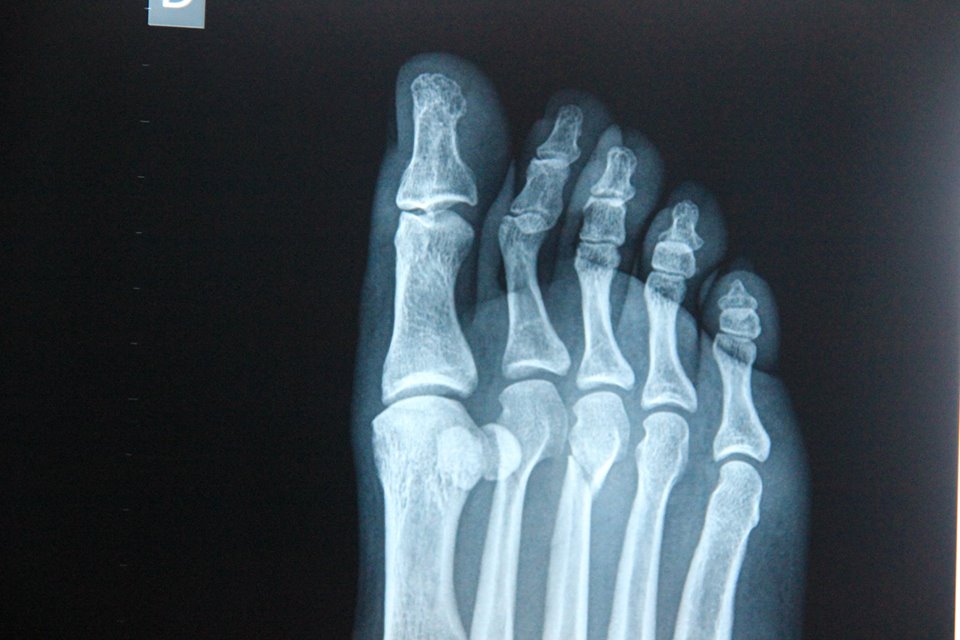

whatsnext2 Published February 6, 2015 at 960 × 640 in whatsnext2 aside from numbers two and three, a perfectly good looking foot